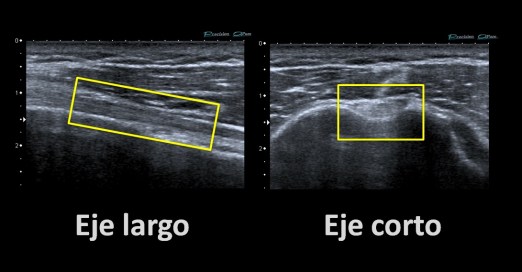

Una cosa más, en ocasiones podemos ver u oír llamar Eje Largo al corte Longitudinal y Eje Corto al Axial, es muy típico de la ecografía muscular. En estos casos, yo prefiero hablar de axial y longitudinal en función de la colocación de la sonda, no del músculo o tendón ya que su colocación puede llevar a error.

Otras denominaciones.

Axial, transverso o eje corto es igual, Longitudinal, eje largo y sagital, también significa lo mismo.